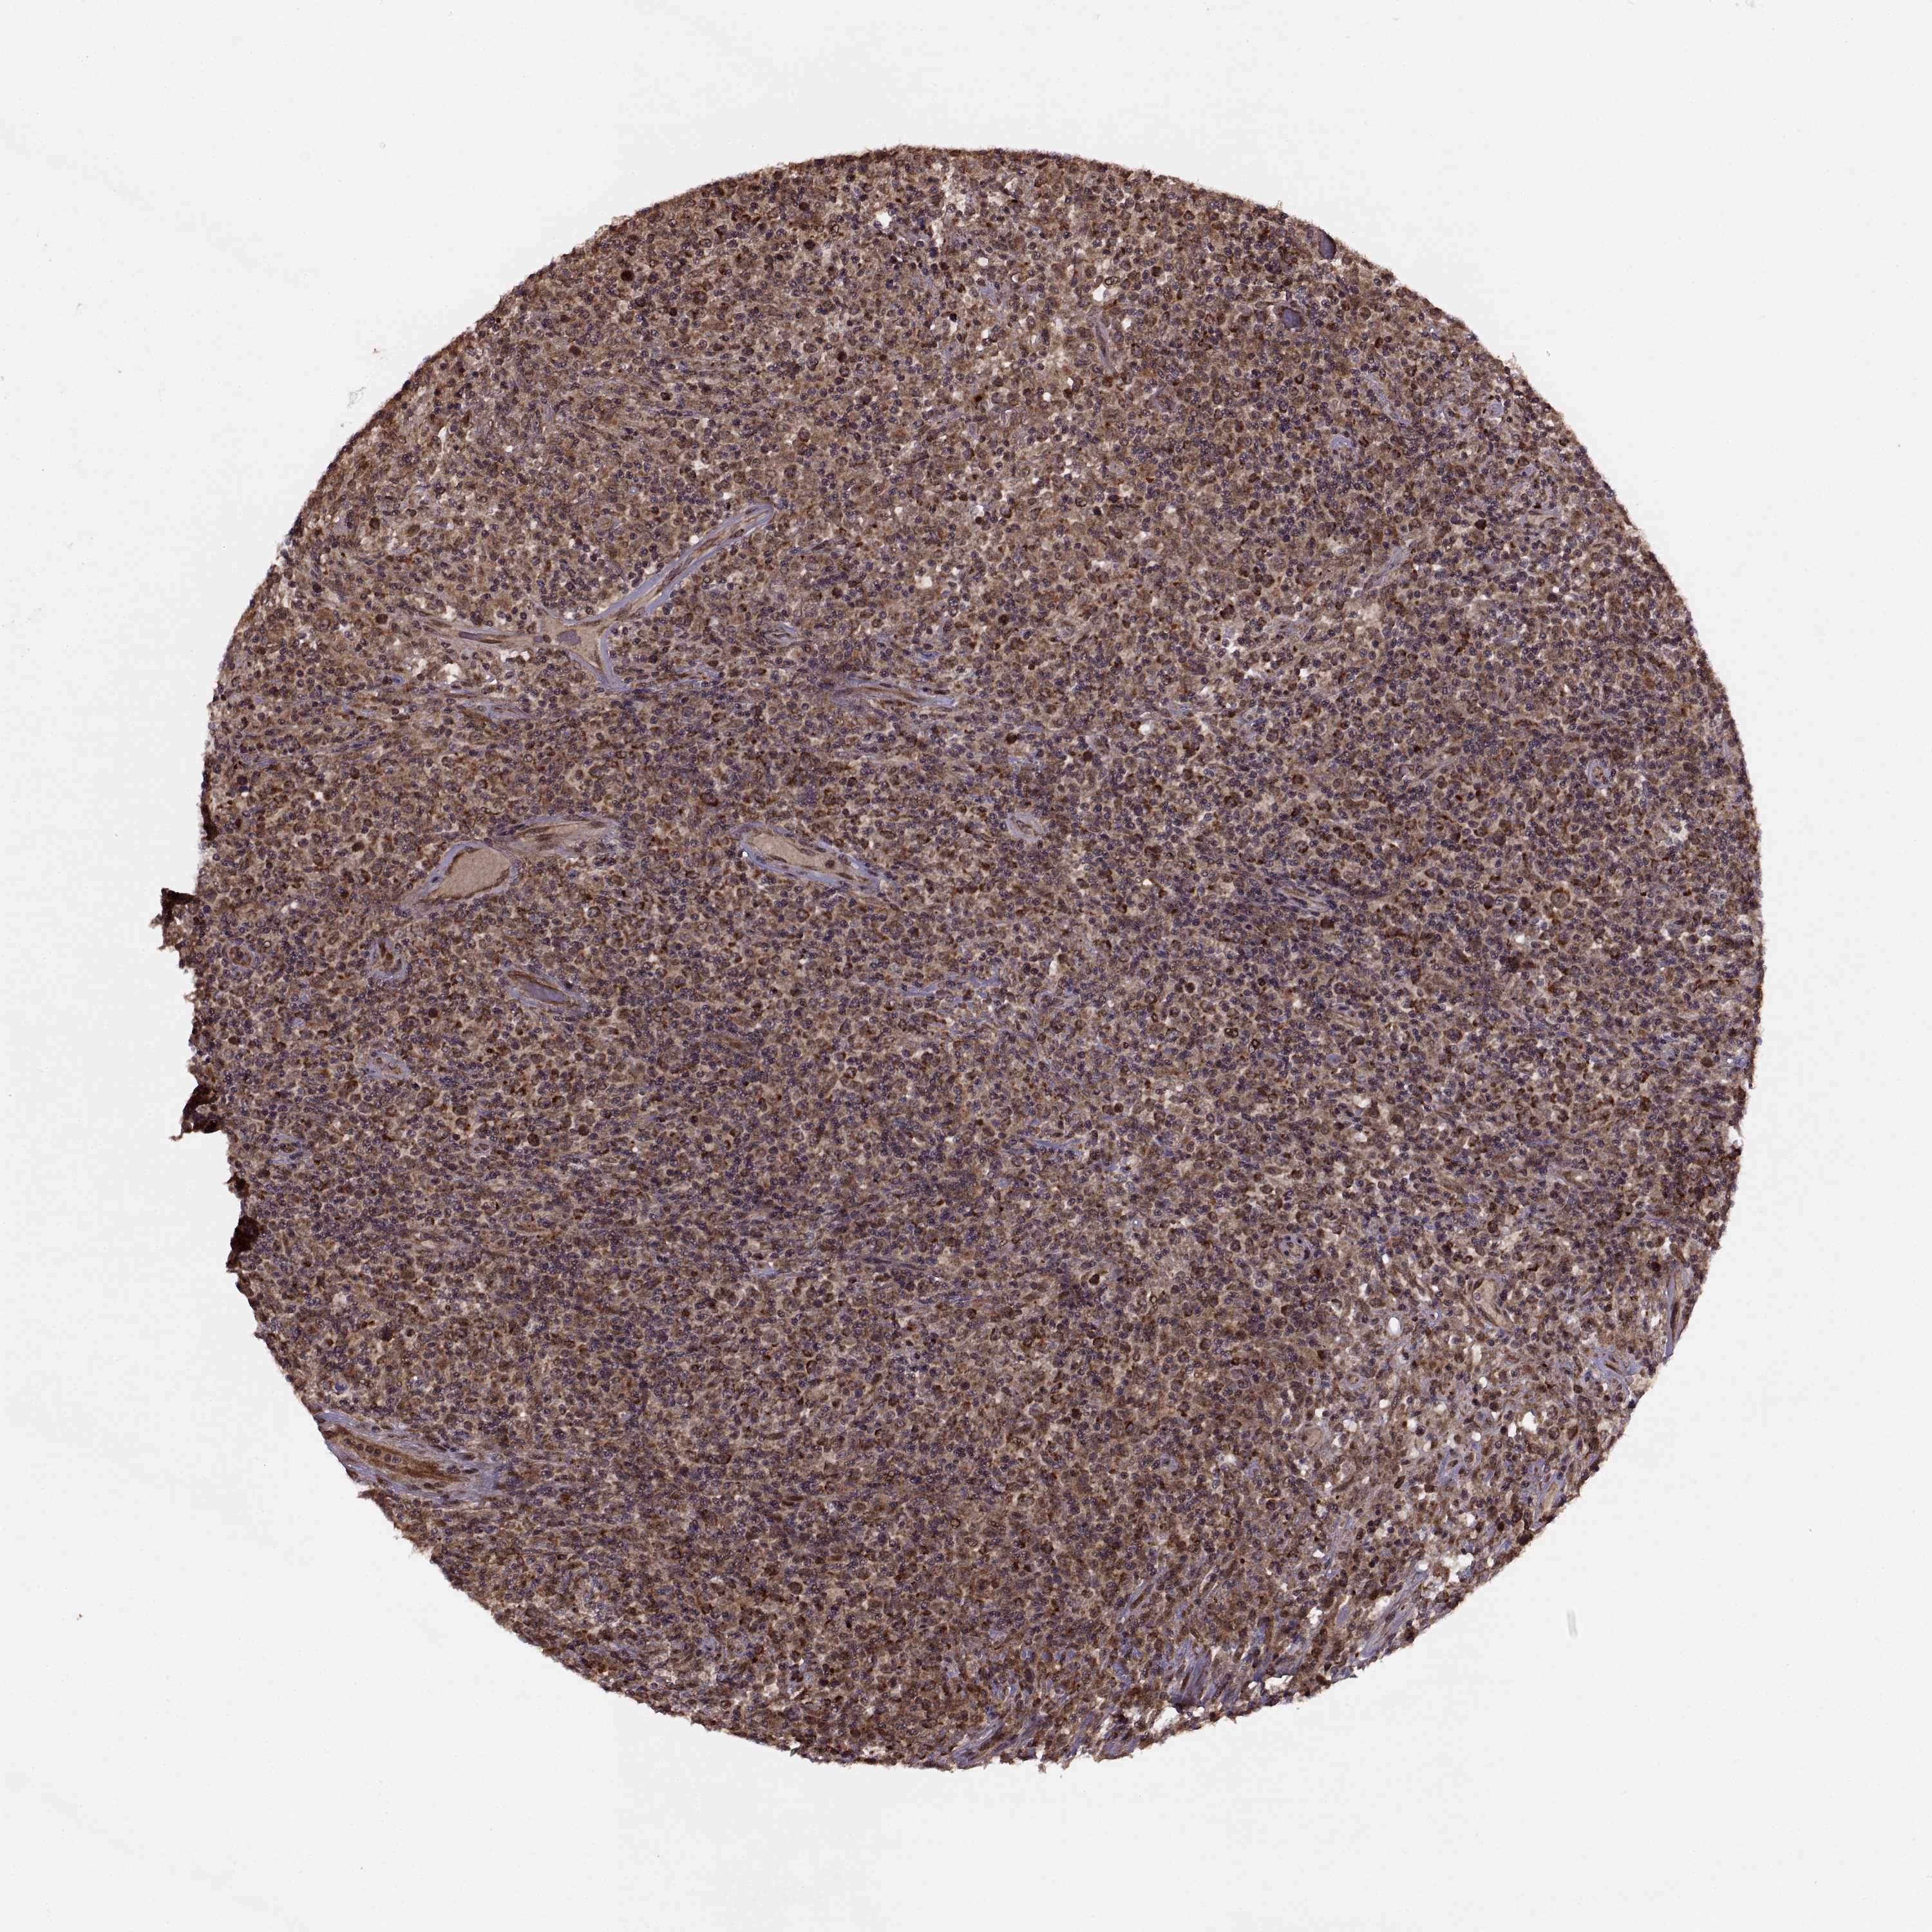

CANCER LYMPHOMA Show tissue menu

LYMPHOMA - Protein expressioni

A mouse-over function shows sample information and annotation data. Click on an image to view it in a full screen mode. Samples can be filtered based on level of antibody staining by selecting one or several of the following categories: high, medium, low and not detected. The assay and annotation is described here.

Each image is clickable and will lead to virtual microscopy that enables deeper exploration of all samples and also displays staining intensity scores, fraction scores and subcellular localization as well as patient and tissue information for each sample.

Antibody HPA075125

Staining

High

Medium

Low

Not detected

Intensity

Strong

Moderate

Weak

Negative

Quantity

>75%

75%-25%

<25%

None

Location

Nuclear

Cytoplasmic/membranous

Cytoplasmic/membranous,nuclear

Malignant lymphoma, non-Hodgkin's type, Low grade

Malignant lymphoma, non-Hodgkin's type, High grade

Hodgkin's disease, NOS